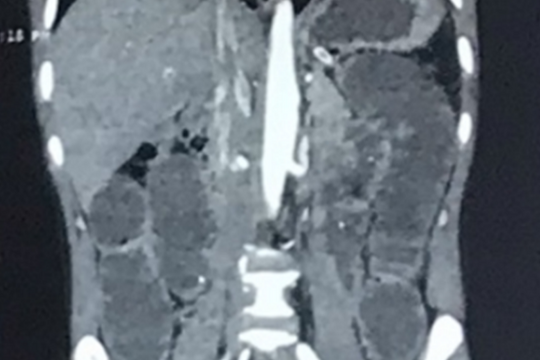

Người đàn ông bụng to như chửa sau 3 năm thường xuyên bị táo bón

Bệnh nhân vào viện trong tình trạng suy kiệt, thể trạng gầy, đau bụng âm ỉ, bí trung đại tiện, vùng hạ vị xuất hiện khối bất thường nổi gồ trên thành bụng.